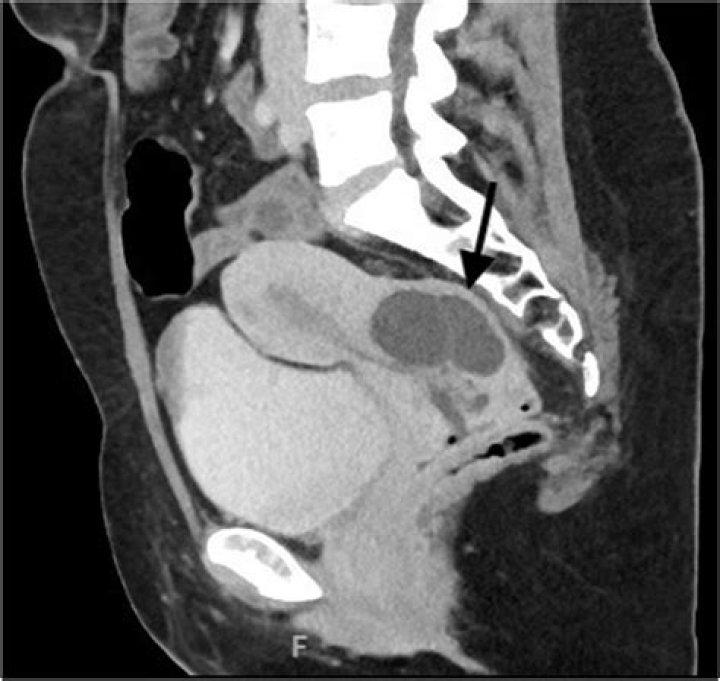

A nabothian cyst is a lump filled with mucus on the surface of the cervix or cervical canal. The cervix is located at the lower end of the womb (uterus) at the top of the vagina. It is about 1 inch (2.5 centimeters) long. The cervix is lined with glands that normally secrete mucus.

Nabothian cysts are mucus-filled cysts that occur on the surface of the cervix. They are usually 0.2 to 0.3 cm in diameter, but they can exceed 1 cm in diameter. In most cases, nabothian cysts reflect the physiological changes in the cervix, but they are sometimes related to chronic cervicitis.

Nabothian cysts (also called mucinous retention cysts or epithelial cysts) are common and benign and are considered a normal feature of the adult cervix (Figure 1, C). Many women have multiple cysts. They may be translucent or opaque, whitish to yellow, and range from a few millimeters to 3 to 4 cm in diameter.